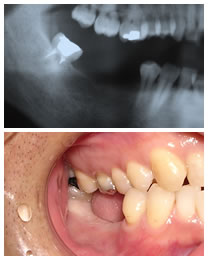

術前レントゲンと術前口腔内写真。患者は30代男性。下顎右側3歯連続欠損にパーシャルデンチャーの制作を説明するが、同意が得られず、固定性の補綴物を希望された。

- そこで、上顎右側8番歯の下顎への自家歯牙移植を計画同意を得る。歯牙移植は適用範囲は多くはないのですが、適用できた場合ブリッジもしくはパーシャルデンチャーにならないですむ利点があります。